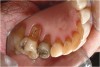

Figure  3  Severe dental erosion and attrition in a GERD patient.

Figure 3

Characteristics of damage to tooth structures caused by acidity include wear on the occlusal surfaces of molars and a saucer shape on the cusps of molars (perimolysis).12 The erosion can vary from minor and subtle changes on the tooth surface, ie, loss of luster, a dull or matted look, to cupping on occlusal surfaces or incisal edges, which may extend to dentin. Usually, the erosive lesions demonstrate greater width than depth. When combined with abrasive forces or stresses, the tooth surface loss may occur at a faster rate (Figure 2, Figure 3, Figure 4 and Figure 5).